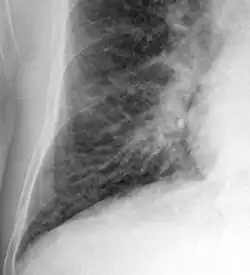

Chest X-ray

Chest X-rays are frequently used to aid in the diagnosis of CHF. In a person who is compensated, this may show cardiomegaly (visible enlargement of the heart), quantified as the cardiothoracic ratio (proportion of the heart size to the chest). In left ventricular failure, evidence may exist of vascular redistribution (upper lobe blood diversion or cephalization), Kerley lines, cuffing of the areas around the bronchi, and interstitial edema. Ultrasound of the lung may also detect Kerley lines.[73]

-

Congestive heart failure with small bilateral effusions -

Kerley B lines